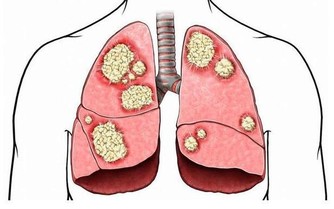

比醬油色尿顏色淺一點的是茶褐色尿,遇到這種尿液就要小心了,很可能提示肝膽腫瘤,

肝臟是代謝膽紅素的器官,如果有腫瘤佔位的話,膽紅素可能從尿液中排泄,於是便產生了茶色尿。